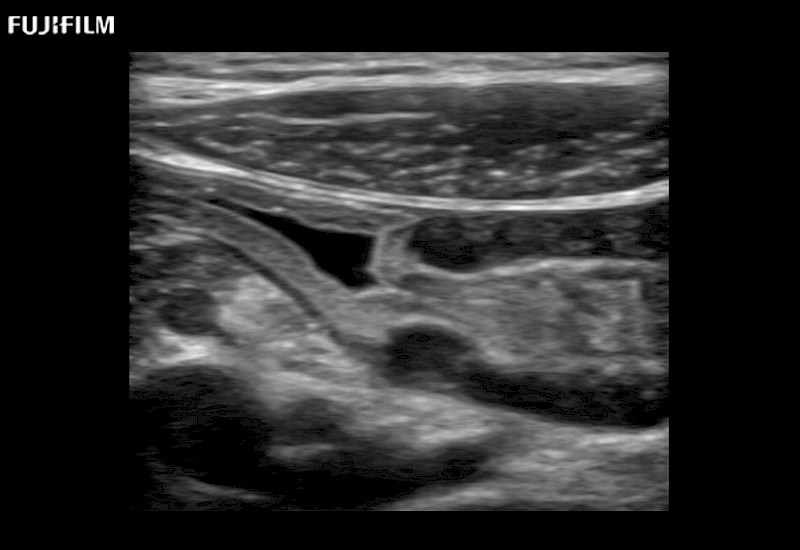

Fujifilm Healthcare understands that Surgical Oncologists demand excellence in their operating rooms — from their staff and the equipment they depend on. Fujifilm Healthcare's dedication to Surgical Oncologists provides outstanding ultrasound technology, professional support and the specialized tools necessary to best perform comprehensive real-time ultrasound imaging.

For precise surgical oncology ultrasound imaging, Fujifilm Healthcare offers premium level solutions that include:

for use during open and laparoscopic procedures: Tumor localization & staging, Ablation, Resection, Biopsy, Transplant, Abdominal exploration, Robotic surgery

Our dedication to Surgical Oncology allows us to offer superior image quality, outstanding system reliability and intuitive use of cutting edge technology.